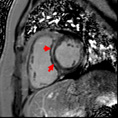

Seeing a Heart Attack. We can visualize heart attacks as bright areas after MRI contrast is given (see red arrows). Approximately, 13% of heart attacks go undetected by standard imaging exams.

Inflammation of the Heart. Not only can MRI visualize heart attacks it can also diagnose other causes of depressed cardiac function such as inflammation or fibrosis of the heart. The red arrows show areas of heart inflammation or myocarditis. No other cardiac test can detect this problem.